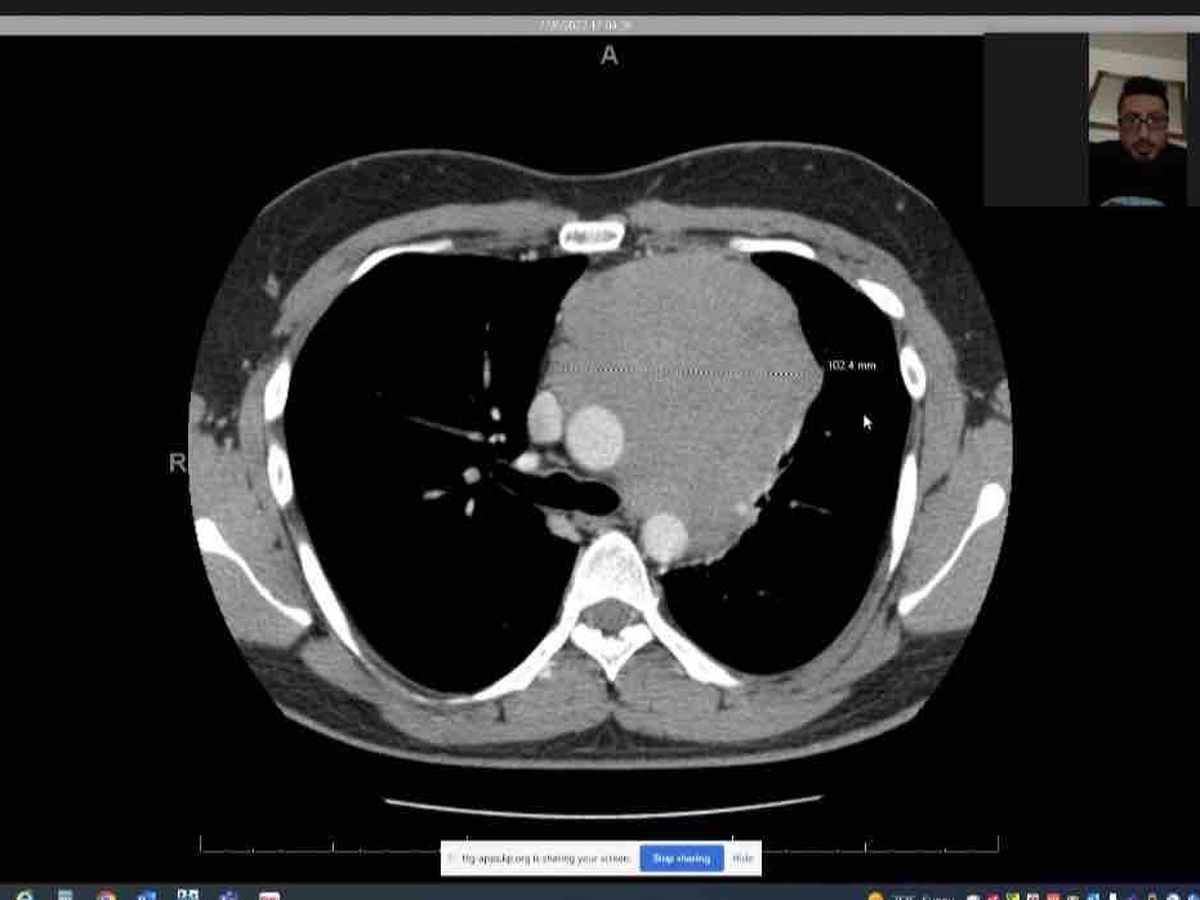

diagnosed with stage 3 mediastinal seminoma cancer in the chest. Seminoma cancer is usually seen in

men in their 20s to 40s and considered